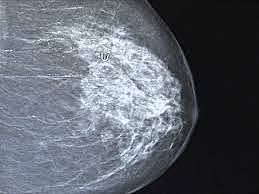

• Imágen mamografica

Imágen mamografica

Primer sistema de imagen mamografica digital directo.